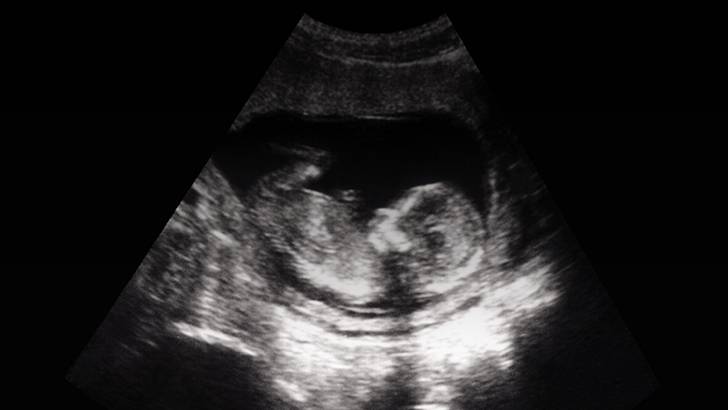

So typically, these issues are identified on the anatomy scan, which tends to be a higher resolution ultrasound between 18, 20, 21 weeks gestation and during that ultrasound, careful attention is paid to major structures, in particular, the brain is at a point where you can accurately assess how it’s developing. If there is an abnormality on ultrasound, we may then do a fetal MRI to get more information, just because there are limitations with ultrasound, in terms of being able to see everything you need to see, based on body positioning and, penetration of the probe. And so then we may do an MRI to get more information.